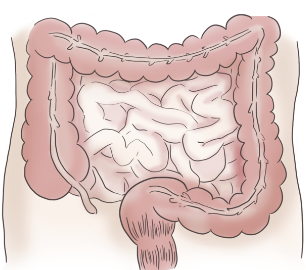

- 대장암: 복부 CT는 대장암 진단에 중요한 역할을 합니다. 대장암은 장의 상피세포에서 암세포가 발생하는 질환으로, 복부 CT를 통해 대장암의 위치와 정도를 파악하여 치료 방법을 결정할 수 있습니다.

- 충수염: 복부 CT는 충수의 염증을 확인하는 데 유용합니다. 충수는 대장의 일부이며, 충수염은 충수의 염증으로 복부 CT를 통해 염증의 정도와 위치를 파악할 수 있습니다.